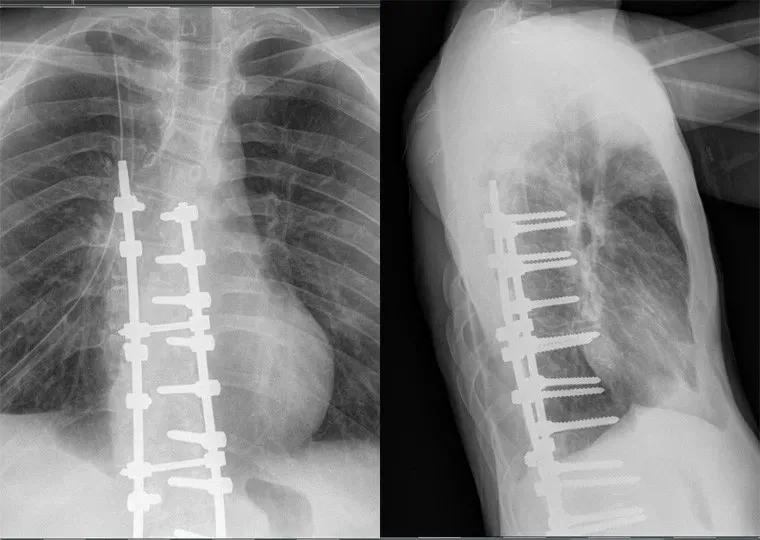

术后康复案例

术后康复 1

该患者接受了脊柱融合手术(T3-L3),手术后没有得到任何康复,甚至有所加重。术后他的头部,颈部和背部都开始疼痛。

患者在融合处上方和下方均具有深部肥大病。需要消除这种情况(使用螺旋稳定器),否则会导致脊柱更快地退化,尤其是在融合上方和下方的部分。由于颈部的紧张和紧绷,患者的头部向一侧弯曲,需要放松和拉伸。该患者在螺旋稳定诊所完成了为期2周的住院治疗计划。

治疗的重点是使头部和颈部与轴线对齐,并激活和加强螺旋肌链和腹壁。SPS团队拉伸了颈部,胸部,髋屈肌和大腿前部的紧绷度。对于经历了脊柱融合手术的患者来说,重要的是要螺旋形地稳定身体并推迟脊柱内退行性变化的发展,螺旋稳定运动为患者的生活提供了再生程序。